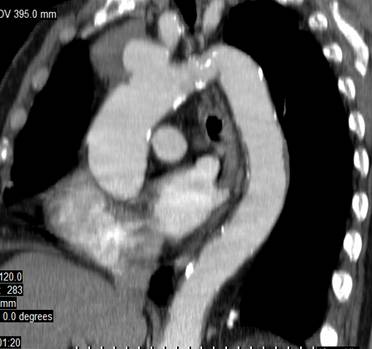

Computer tomografia : a evidentiat anevrism sacciform de crosa aortica, cu dimensiuni de 3/3,5 cm, situat la emergenta trunchiului arterial brahiocefalic, coletul anevrismal incluzand emergenta acestuia, tapetat de tromb parietal cu grosime de 3 cm, tromboze si calcificari parietale la nivelul aortei toracice si abdominale (Fig.6).

Fig.6 Tomografie computerizata: anevrism sacciform de crosa aortica, partial trombozat.